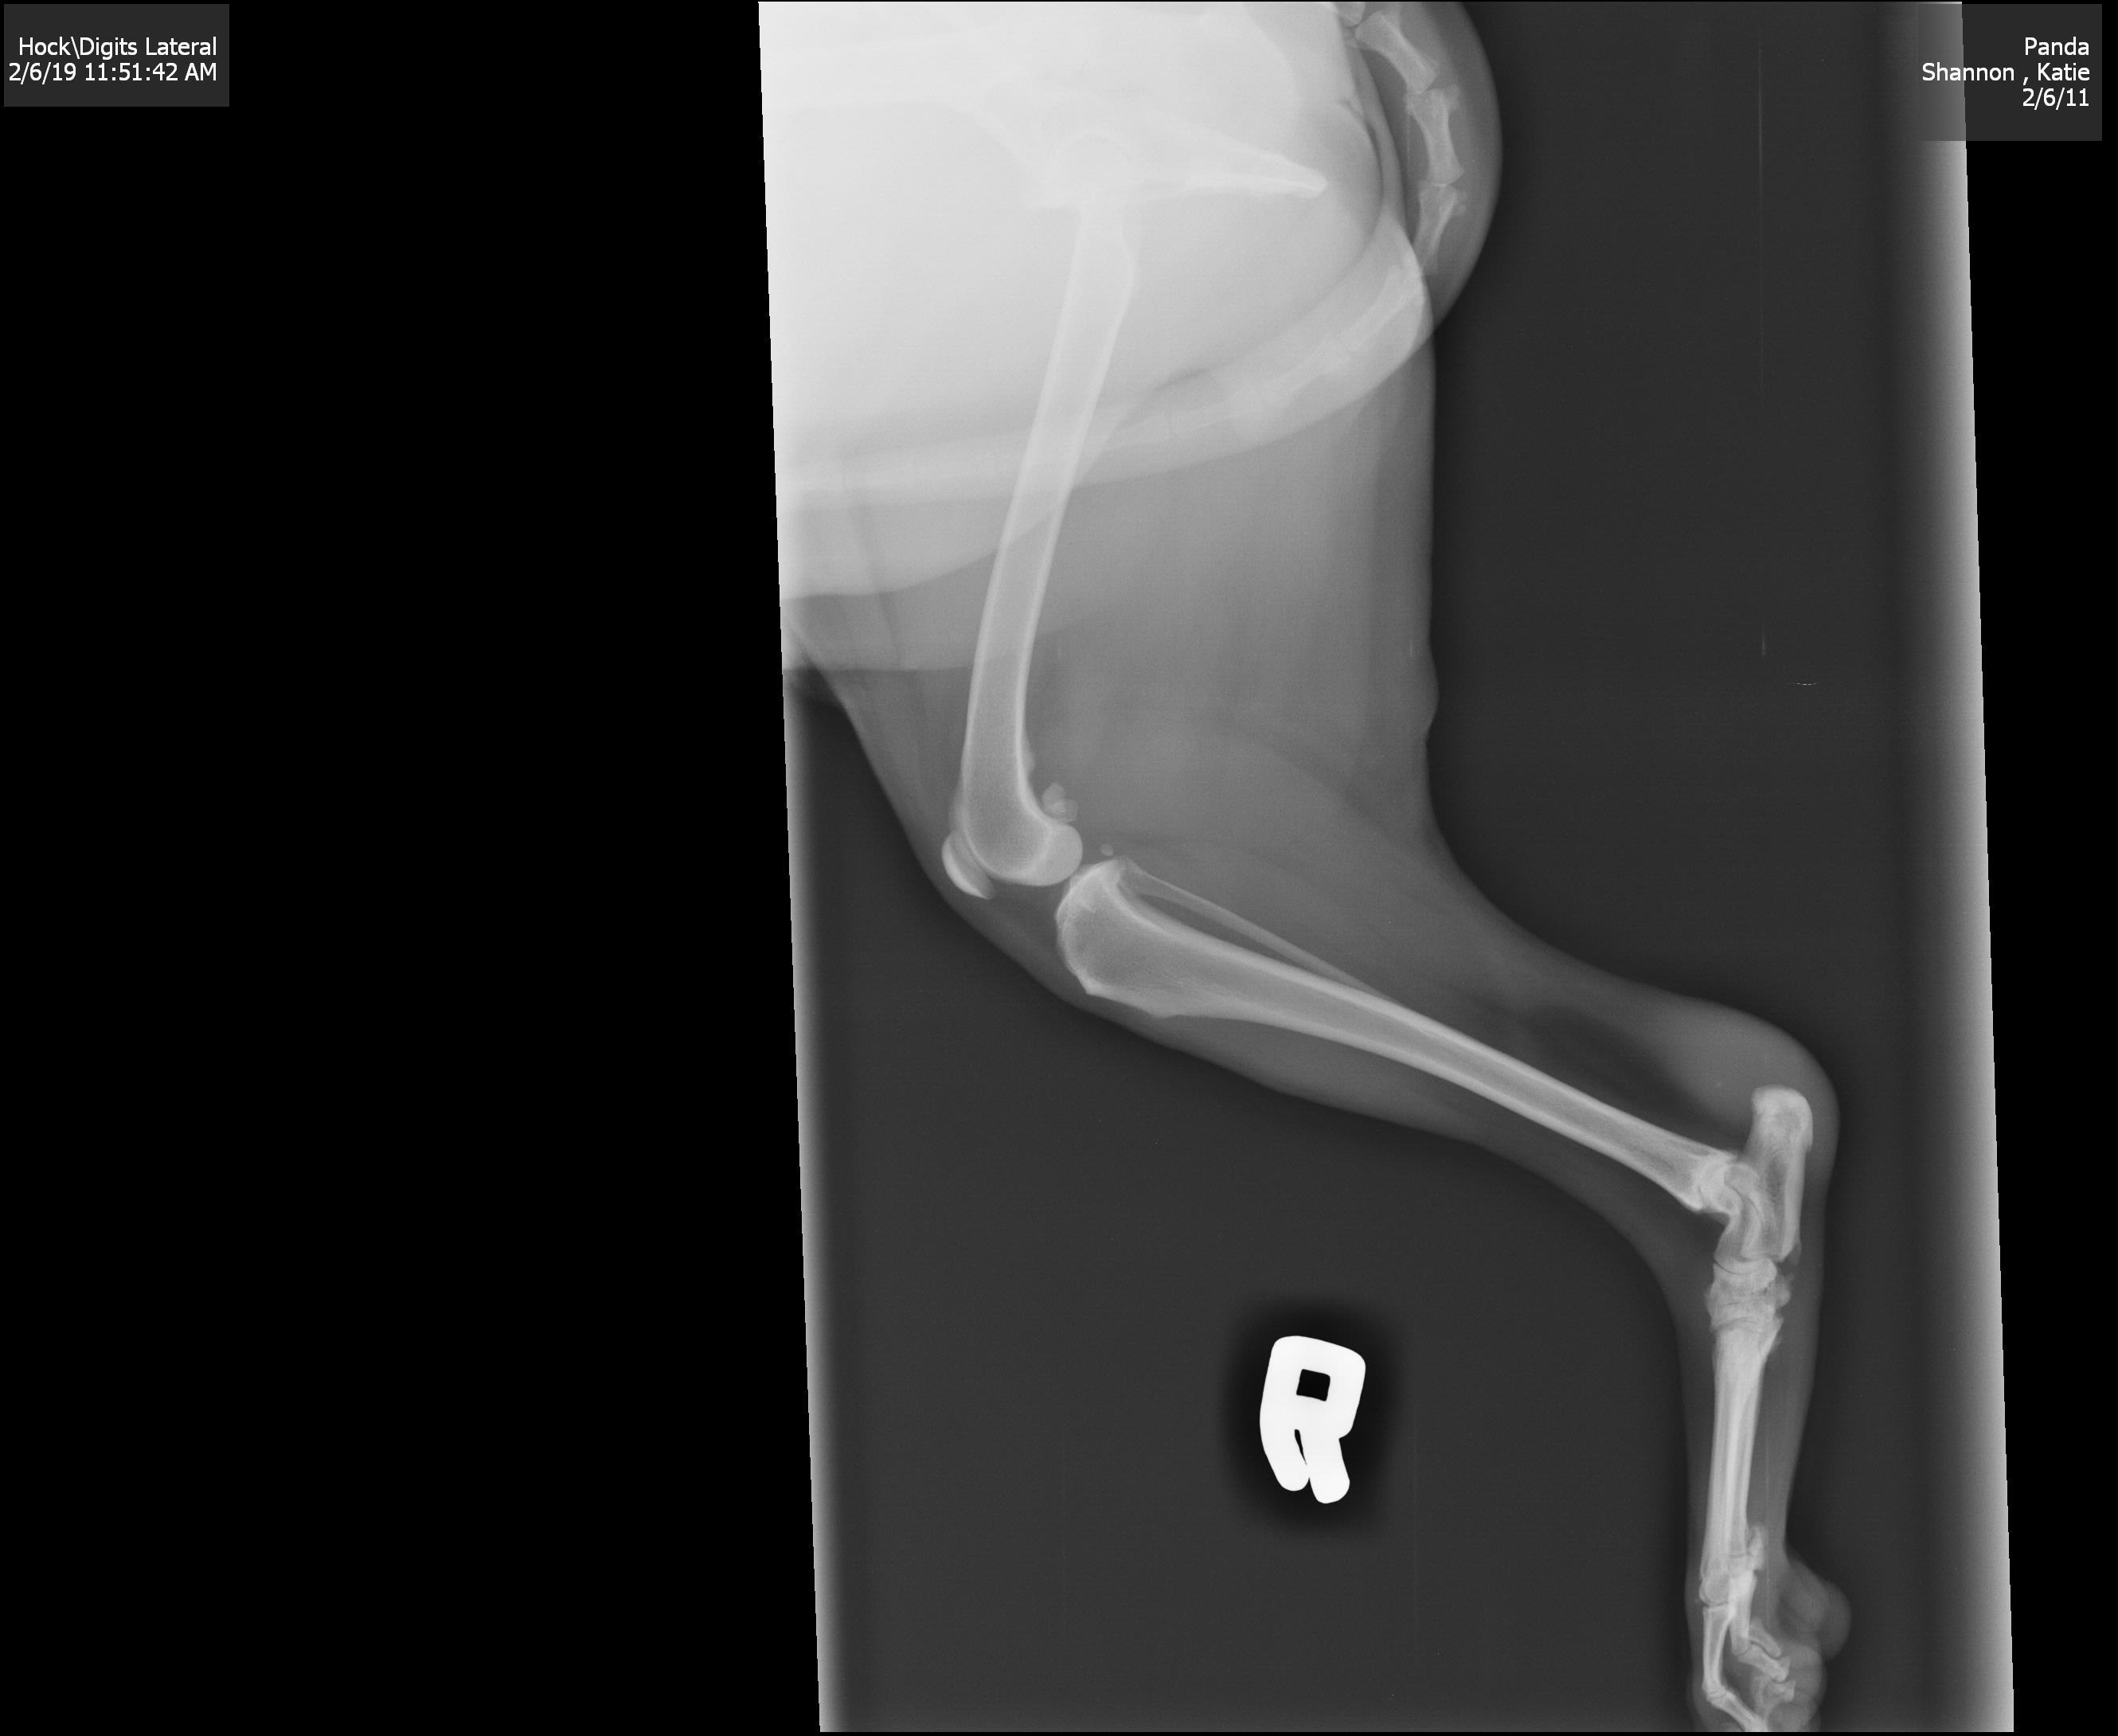

Not lamesudden swelling of hock. Feels like the tendon and joint are involved. Squishy and feels like grissel. Hot. Took her to vet for xray, waiting for more followup in a few days. Im so worried about cancer after losing a dog a year ago. Put her on Meloxicam to see if it reduces inflammation. Been a few days and now the swelling hasnt really gone down but the joint feels harder and less squishy, about the same size and noticeably visible. Do you think we are dealing with cancer or an injury?

I cannot give you a definitive answer to your question just by looking at the is one x-ray. I can't get a good look at the x-ray as it won't enlarge enough for me to see what I need to see. Regardless, I think I see a lucent area on the calcaneous. That could be cancer but it could be osteomyelitis (bone infection) or even a fungal infection. It does not appear to involve the joint. The calcaneous is not at typical area to get bone cancer if that is any consolation. It is not impossible, just not common. This could be a hygroma (inflammation of the bursa) but without examining her myself it is too hard to say. I think your vet needs to aspirate the mass and look at the fluid under the microscope - usually you can see if there is bacteria in there (I would be worried about this so she really should be on some antibiotics) or cancer cells or just inflammation, etc. ( https://www.drsfostersmith.com/pic/article.cfm?articleid=2847 ) Hope this helps. Best wishes.